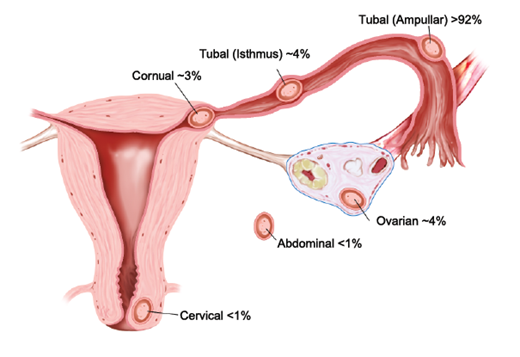

Извънматочната бременност

Публикувано на: 09.01.2007 Извънматочната бременност – това е състояние, при което оплодената яйцеклетка се прикрепва и започва...

ПовечеЕктопичната бременност

Публикувано на: 09.01.2007 "Ектопичната бременност (ЕБ) е описана за първи път от Riolan (1626 год.), но и до днес създава сери...

ПовечеИзвънматочната бременност

Публикувано на: 05.11.2003 Това е бременност, при която оплодената яйцеклетка вместо да премине през една от фалопиевите тръби ...